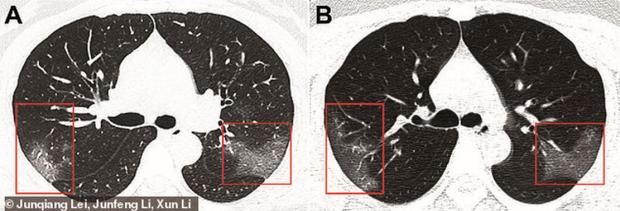

The First Hospital of Lanzhou University au publicat în revista Radiology radiografiile unei femei, de 33 de ani, infectată cu virusul ucigaș, ce arată efectul crunt pe care îl are asupra plămânilor.

Așadar, femeia a fost diagnosticată cu noul coronavirus, după ce s-a remarcat numărul extrem de scăzut de celule albe din sânge, ceea ce înseamnă că avea o infecție în corp. În radiografii se poate observa cum virusul se extinde în organism și îi acaparează plămânii.